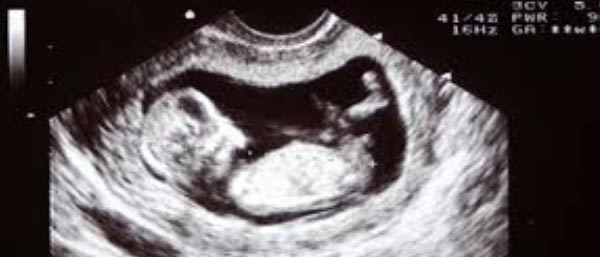

കോട്ടയം: സ്കാനിംഗ് സെന്ററുകൾക്കു മൂക്കുകയറുമായി ആരോഗ്യ വകുപ്പ്. ഗർഭസ്ഥ ശിശുവിന്റെ ലിംഗ നിർണയം നടത്തുന്നതല്ലെന്ന അറിയിപ്പ് സ്കാനിംഗ് സെന്ററുകളിൽ പ്രദർശിപ്പിക്കണമെന്നാണ് ആരോഗ്യ വകുപ്പ് നിർദേശം. ഭ്രൂണലിംഗ നിർണയം നിരോധിക്കുന്ന പി എൻഡിടി നിയമം പാലിക്കാത്ത സ്കാനിംഗ് സെന്ററുകൾക്കെതിരെ നടപടി സ്വീകരിക്കുമെന്ന് പിഎൻഡിടി നിയമം നടപ്പാക്കുന്നതിന്റെ ചുമതലയുള്ള ജില്ലാതല മോണിട്ടറിംഗ് കമ്മിറ്റി യോഗത്തിൽ ജില്ലാ മെഡിക്കൽ ഓഫീസർ ഡോ. ജേക്കബ് വർഗീസ് താലൂക്ക് ആശുപത്രി സൂപ്രണ്ടുമാർക്ക് നിർദ്ദേശം നൽകി.